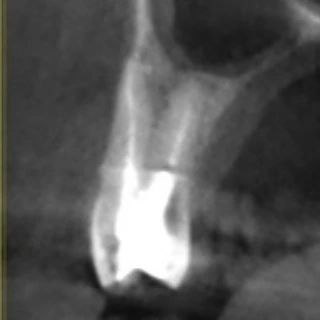

Распространенность: 1 премоляр вч - 3.2%, 2 премоляр вч - 0.4%

- проводить аккуратное расширение щёчных каналов, так как в области данных корней очень мало дентина (в моём случае расширение 25.04)